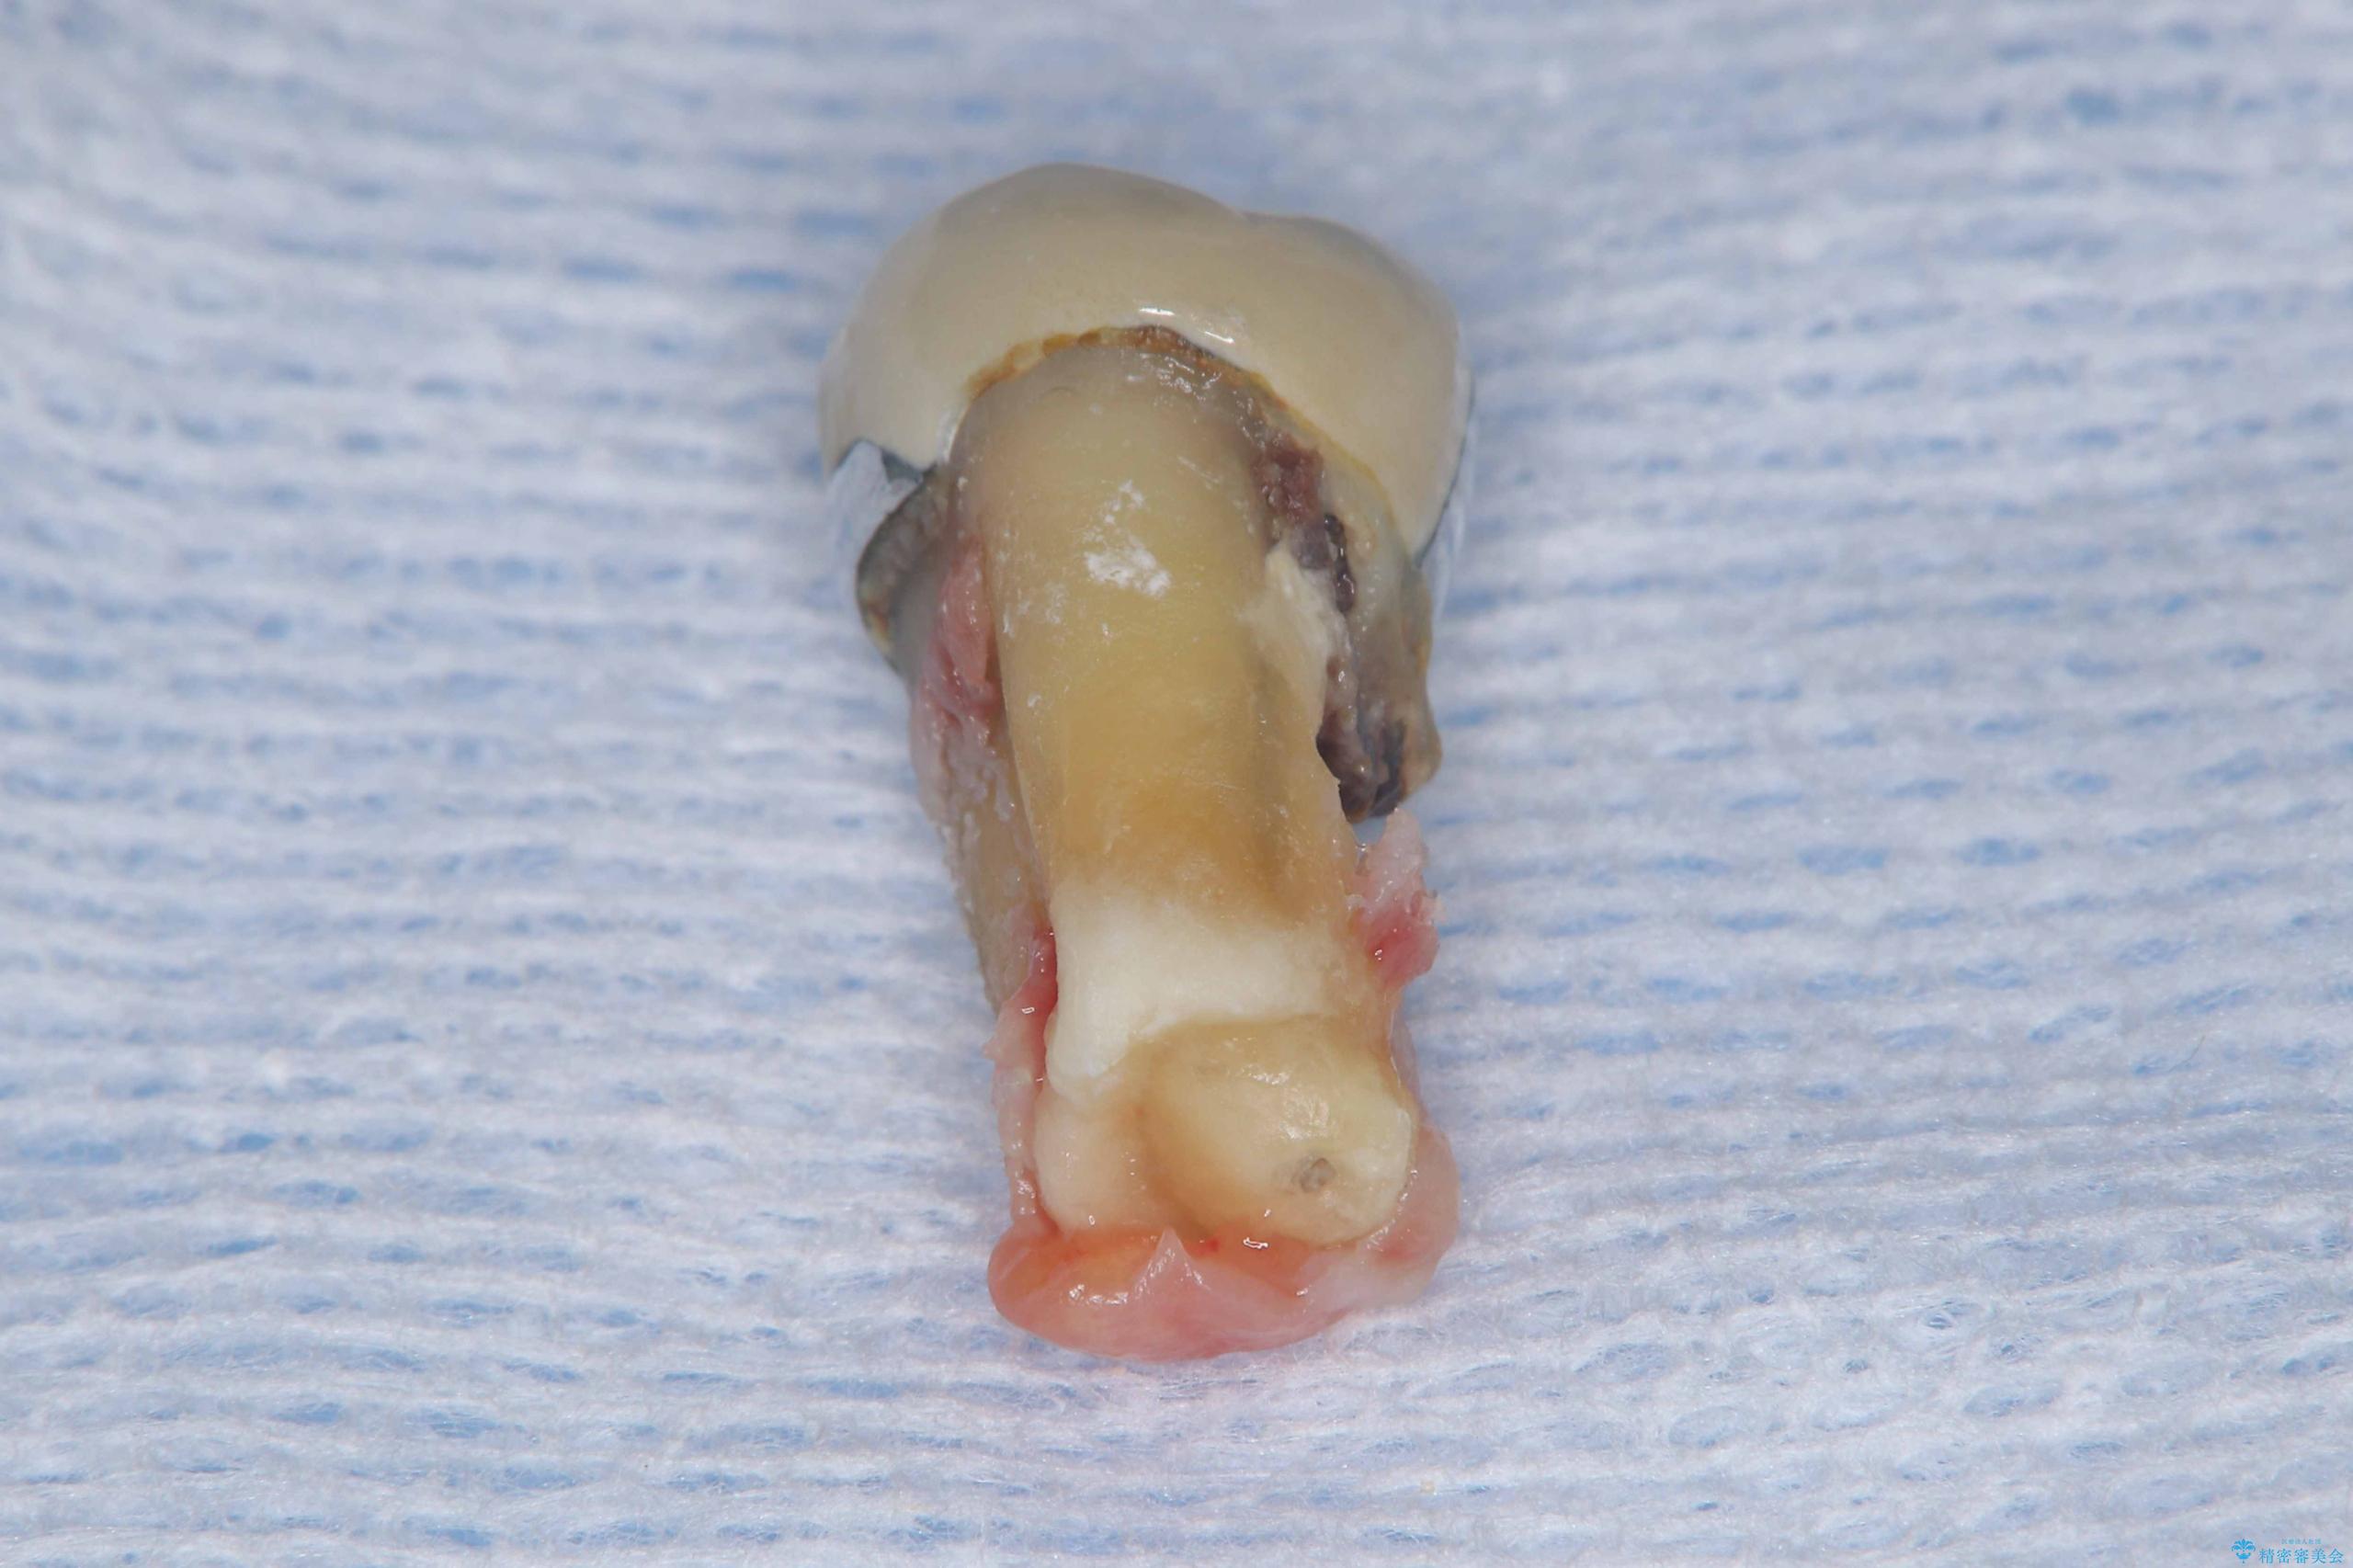

- 過去にヘミセクションが行われていたと思われる左下7番は、大きな歯根嚢胞および根尖病変が認められ、さらに骨縁下カリエスを伴っており、歯肉には瘻孔が形成されている状態でした。

保存は困難と判断し、左下7番は抜歯即時インプラントによる治療を行いました。